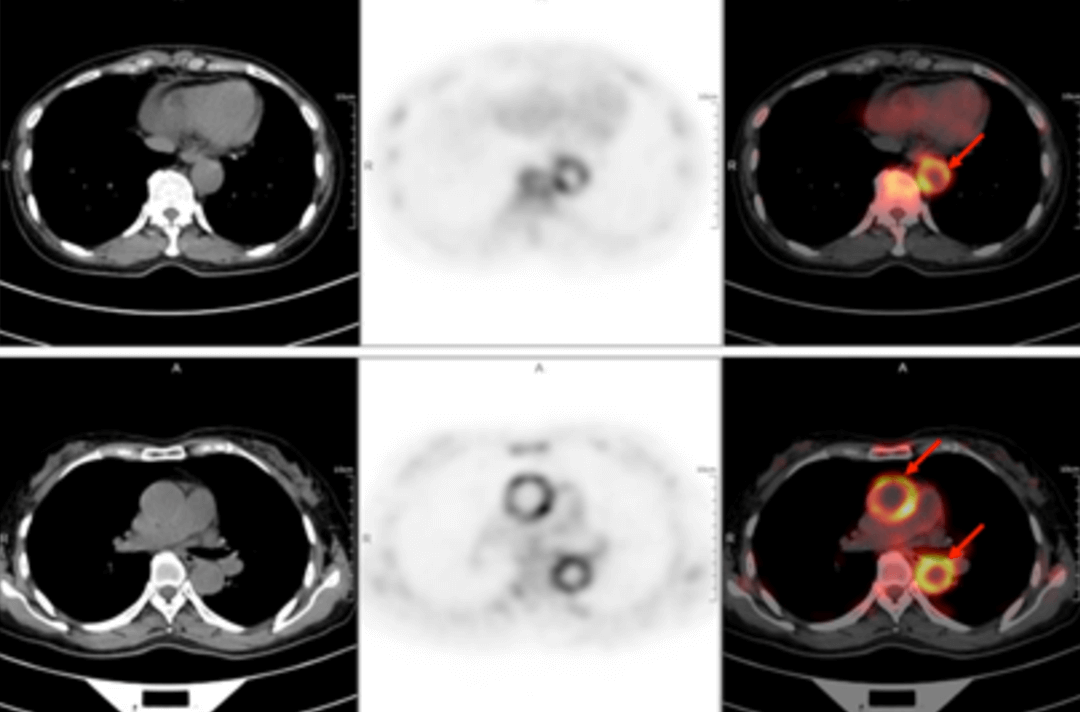

58歳の女性が40日以上前から断続的に発熱しているため受診しました。体温は38.9℃で、寒気、痰、喀血、胸痛、胸部圧迫感、息切れなどの症状はなく、倦怠感、肩関節痛が午後から夜間にかけて特に強く現れました。セファロスポリン系抗生物質の静脈内投与を2週間続けても改善は見られず、断続的な発熱が続いていました。外来診療では「原因不明の発熱」と指摘され、身体検査では明らかな診断上の特徴はありませんでした。血液検査の結果は以下の通りでした。赤血球沈降速度(最初の1時間):72mm、高感度C反応性蛋白:204. 20mg/lでした。その後、原因不明の発熱の原因を探るため、全身 F-FDG PET-CT 検査を行いました。

PET/CT 画像では,全身数カ所(両側内頚動脈,総頚動脈,腕頭動脈,両側鎖骨下動脈,腋窩動脈,胸部大動脈,腹部大動脈,両側総腸骨動脈,内腸骨動脈,外腸骨動脈,大腿動脈)に糖代謝亢進を伴う壁厚化を認め,炎症性変化によるものと判断しました。病歴、臨床症状、検査、画像所見を総合してT.A.と診断し、標準的な抗炎症治療を行ったところ、体温が低下し病状が改善しました。